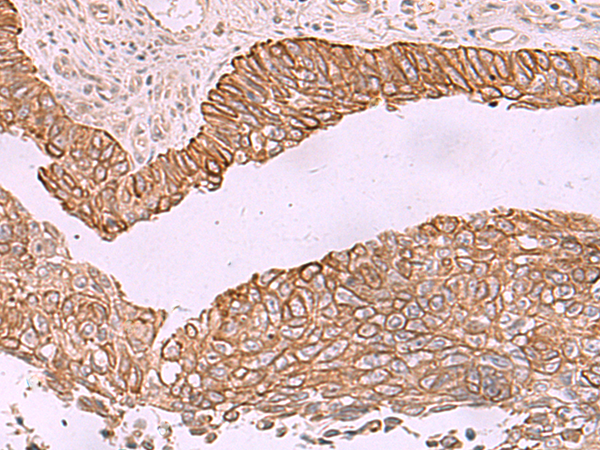

IHC positive control: |

Human lung cancer |